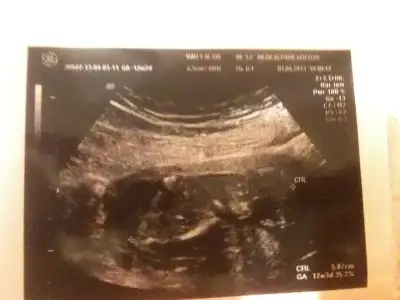

dr soylemeden siz gorun genital nub teorisi ( bebegin cinsiyeti)

anlayan arkadaşlar sizce nub belli mi cinsiyet konusunda bir fikriniz var mı?

11.haftada dr. cinsiyetine önce kız dedi, sonra pipi gördüm dedi, sonra da kordon olabilir dedi, yani bilemedi, orkidem kız demişti. 16.haftada başka bir dr. %98 kız dedi.

18.haftada kendi doktorum erkek dedi ve pipiyi gösterdi.

lakin biz emin olamadık, kafamız karıştı.

21.haftada ayrıntılı ultrason için gittiğimiz perinatoloji uzmanı (prof.) erkek dedi, biz de gördük pipiyi.